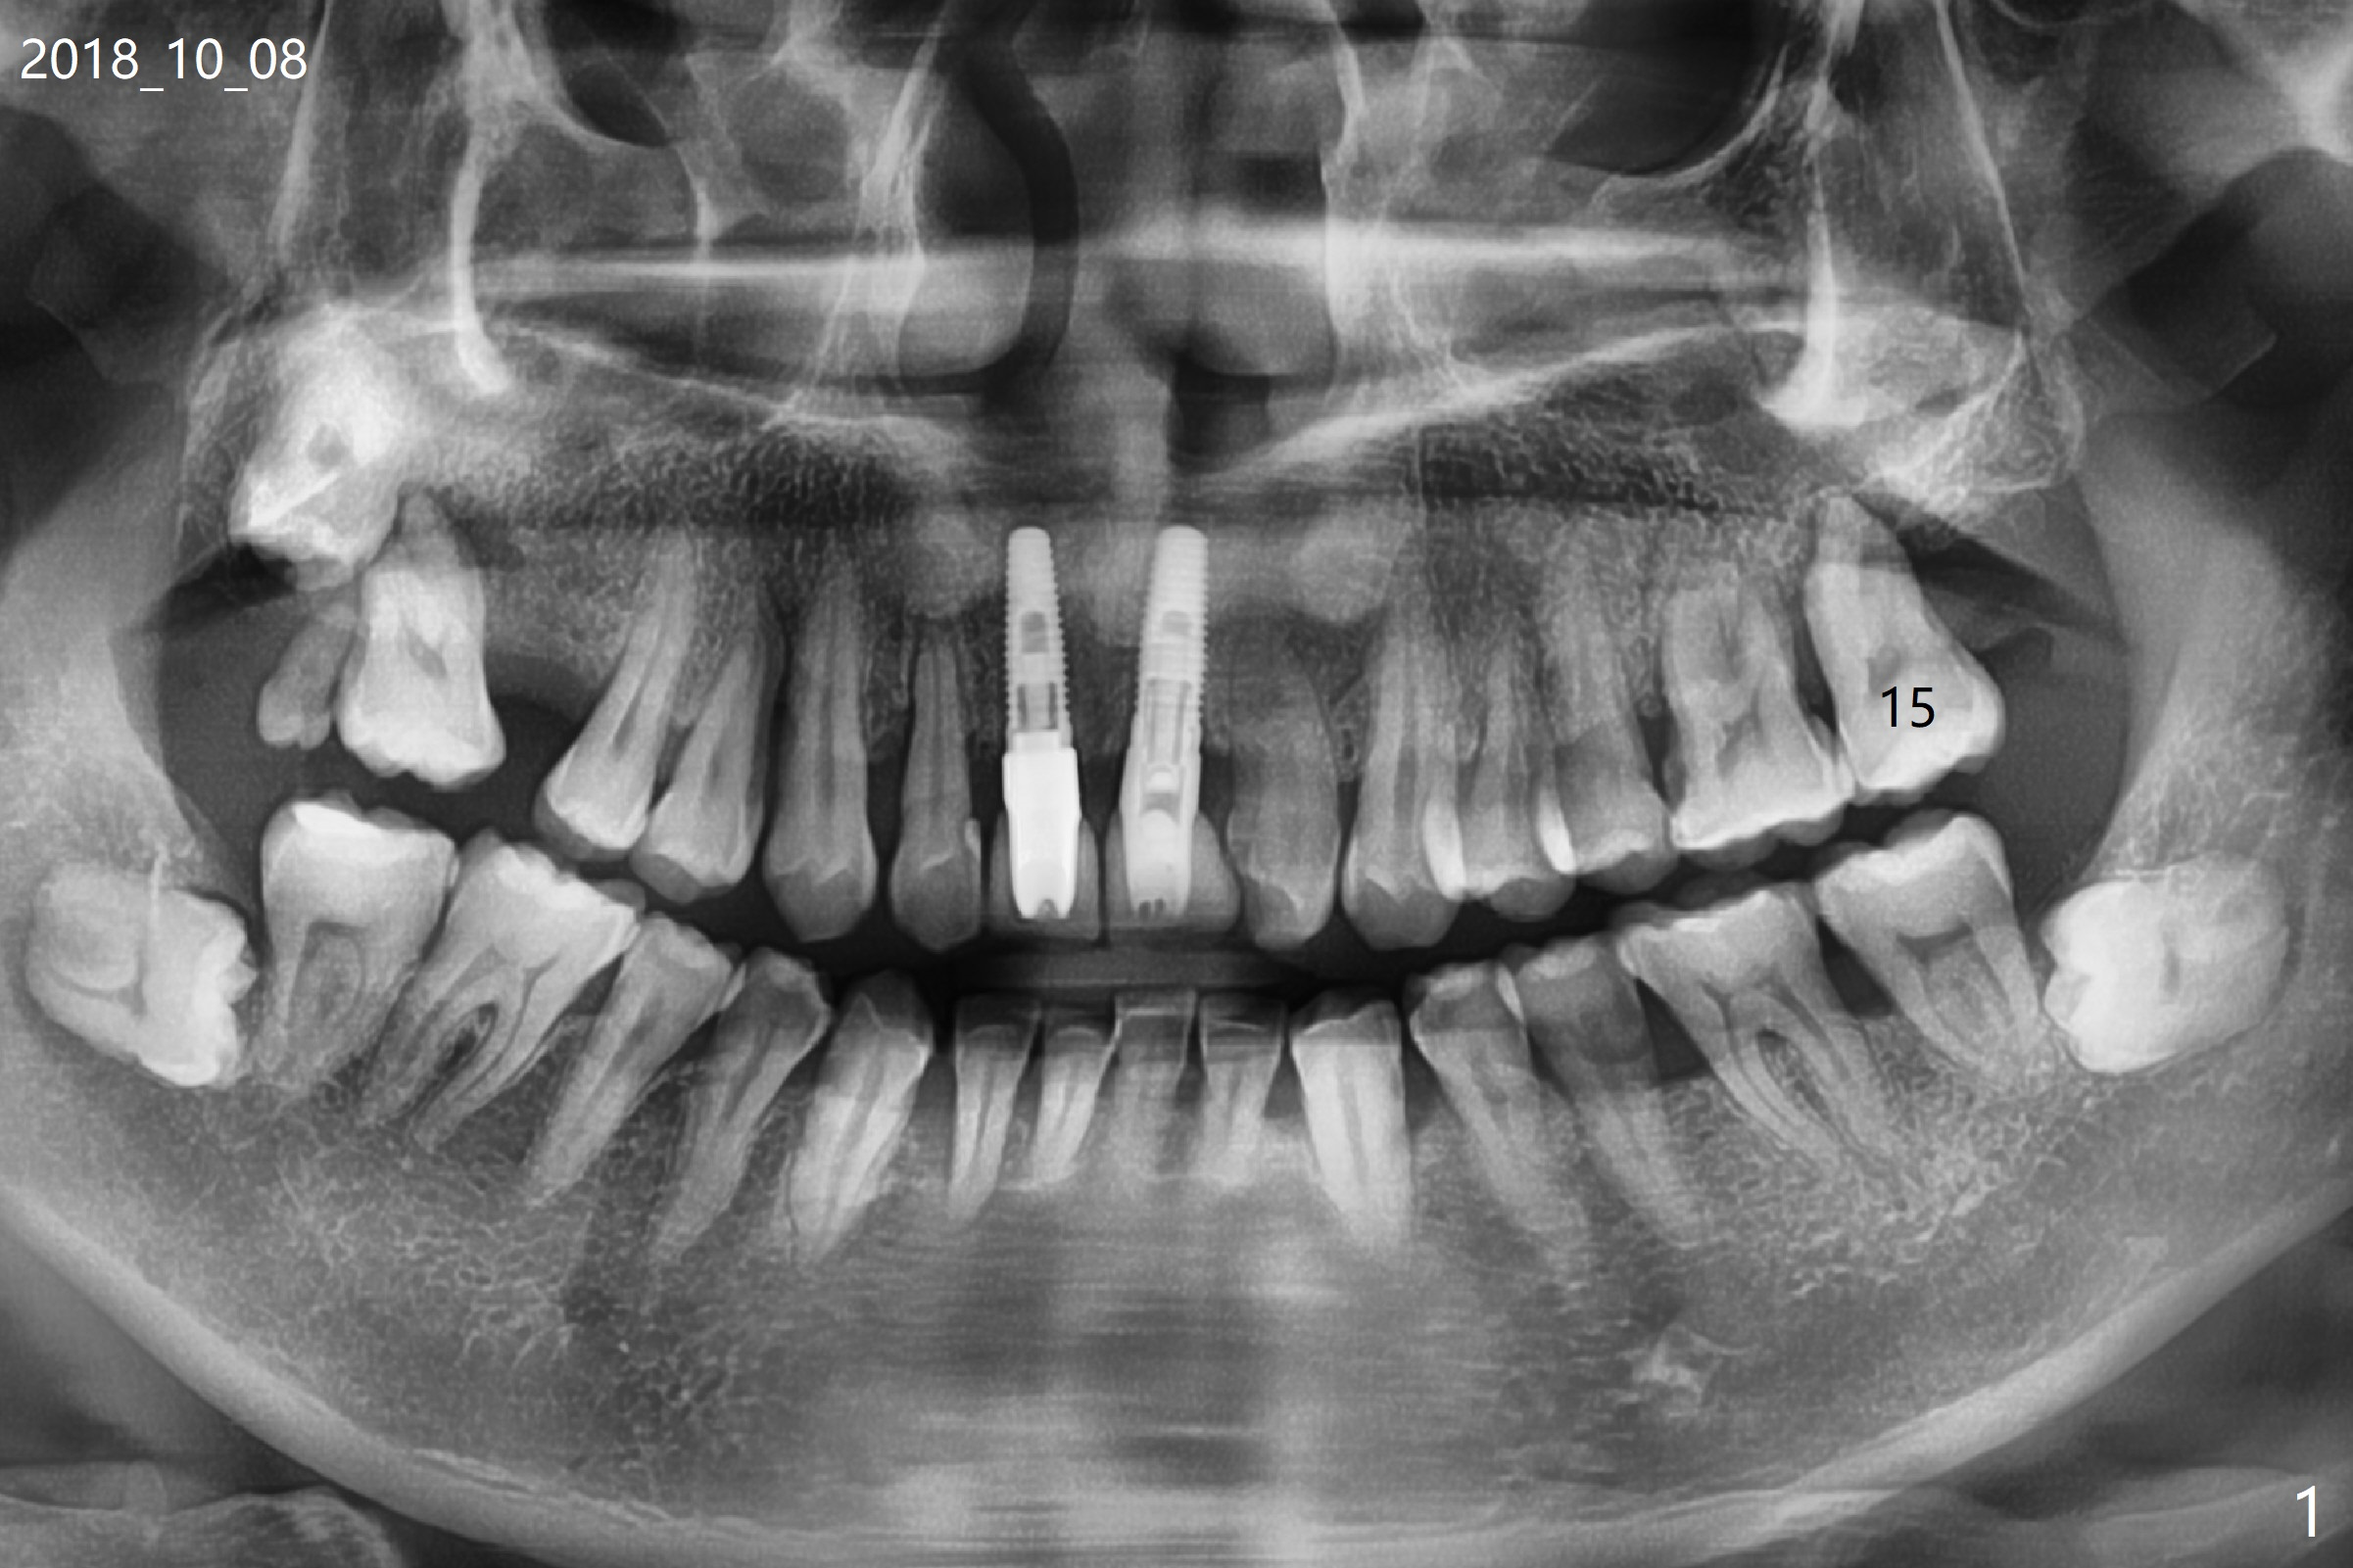

A 54-year-old man returns to clinic 5 months post SRP with chief complaint of UL loose tooth (#15, Fig.1). Since the remaining bone is limited after extraction, it is apparently unsuitable for immediate implant (Fig.2). Socket preservation seems to be able to gain bone height near gingival margin (Fig.3 red line). In fact 1 cc of cortical and cancellous bone mixture is used; after heavy debridement the bone graft is deposited on the distal root surface of the tooth #14 (Fig.4 arrow). The bone increases not only coronally, but also apically (Fig.5 blue lines, as compared to red lines denoting the original bone height). The bone reduces in height 10 months postop (Fig.6). Sinus lift is required for placement of a short implant (Fig.7). Socket preservation does not prevent post-extraction bone loss.